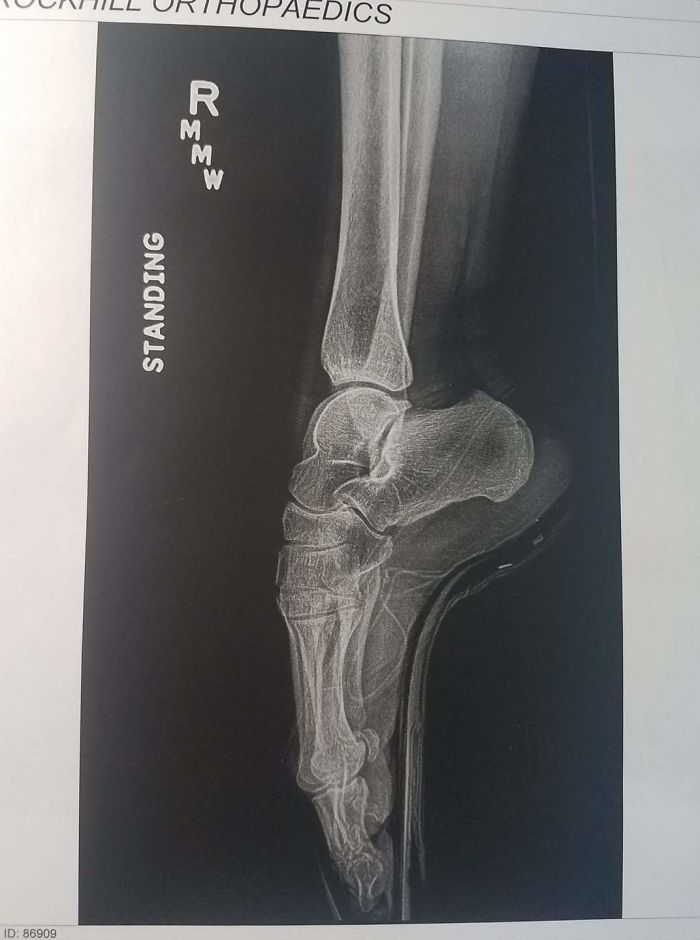

"Моя жена балерина, и это ее рентгеновский снимок в пуанте"